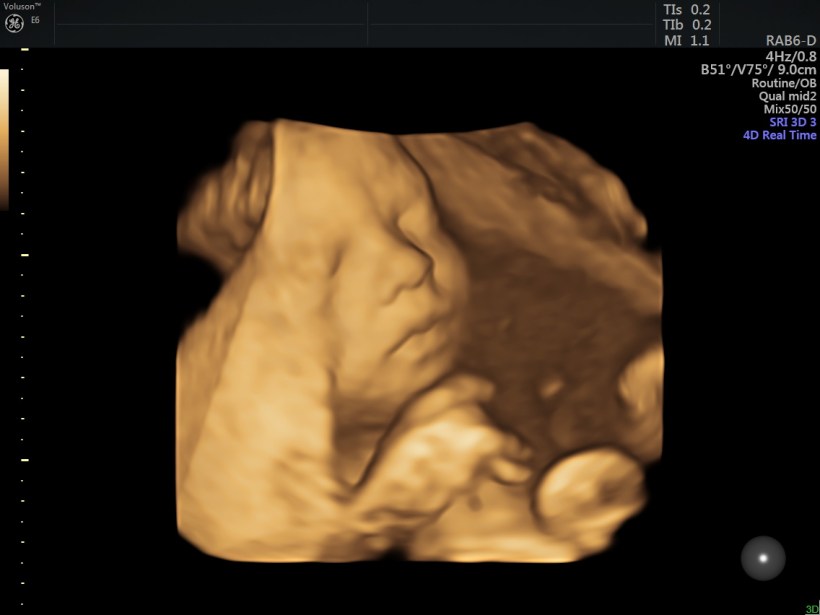

Some of you follow every blog post and I love how supportive you are for us!  Today I wanted to keep this short and sweet (extra sweet) and share some recent baby photos we received a few weeks ago!  My heart is full and just can’t wait to have this chunky little baby boy in my arms.

Image_50 (2)

Of course, like his parents he does his best to steer clear of the camera and is also a bit stubborn.  Out of the 50 photos we received, these were the ones we could see his sweet face the most.  Although chunky and adorable, he is mighty!  🙂